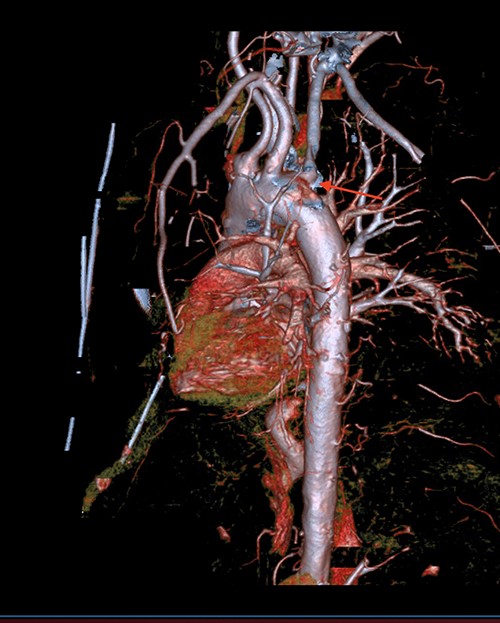

A 71-year-old male with past medical history of type 2 diabetes and hypertension presented to the emergency department at St. Joseph’s University Medical Center with severe respiratory distress. On nonrebreather, the patient’s oxygen saturation was 49%. The patient was subsequently intubated. Evaluation revealed pneumonia secondary to COVID-19 leading patient to be intubated on ventilator support for 4 weeks. During this time patient was maintained on enteral feeding through nasogastric tube, and was on gastrointestinal prophylaxis Protonix 40 mg daily for the duration of his admission. Ultimately, the patient made full recovery and was sent home; however, approximately 3 weeks later, he presented to the emergency department due to syncope. The patient experienced large-volume bright red hematemesis. He became hypotensive and was transfused three units of packed red blood cells and started on pressors. The patient was intubated and transferred to the intensive care unit (ICU) with acute blood loss anemia and hypovolemic shock. Here, an esophagogastroduodenoscopy (EGD) was performed revealing midesophageal bleed (Fig. 1). Hemostasis was achieved with clipping; however, post-procedurally, the patient again became hypotensive. Repeat EGD showed a nonbleeding esophageal ulcer with three clips in good position (Fig. 2). Computed tomography (CT) angiogram of the thorax was performed revealing an actively bleeding aberrant right subclavian artery perforating into the esophagus (Figs 3 and 4). The right subclavian artery was noted to be of normal caliber without ectasia or aneurism and the esophagus was free of any other pathology. Thoracic and vascular surgery were consulted; however, the bleed was deemed of nonsurvivable pathology due to comorbidities and current clinical status. Ultimately, the family of the patient decided to withdraw care and the patient passed.

CT thoracic showing the arch of the aorta with the take-off of the right subclavian artery (red arrow) distal to the left subclavian artery.